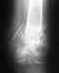

Re: перелом Ладьевидной кости кисти

что посоветуете по поводу этой операции и где и кто может её провести?

Бессистемный поиск в сети "лучшей операции" - без базовых знаний в предметной области - создает иллюзию легкости решения проблемы.

Коротко говоря, пациенту не нужно самому искать оптимальный метод лечения. Для этого есть профессионалы, специалисты именно по этой проблеме, которыми являются даже не все врачи, не то, что пациенты.

Надо обратиться в отделение хирургии кисти, которое имеет большой опыт в лечении несращений ладьевидной кости. Пусть там специалисты высокого класса выбирают из множества существующих операций ту, которая соответствуют конкретному варианту несращения.